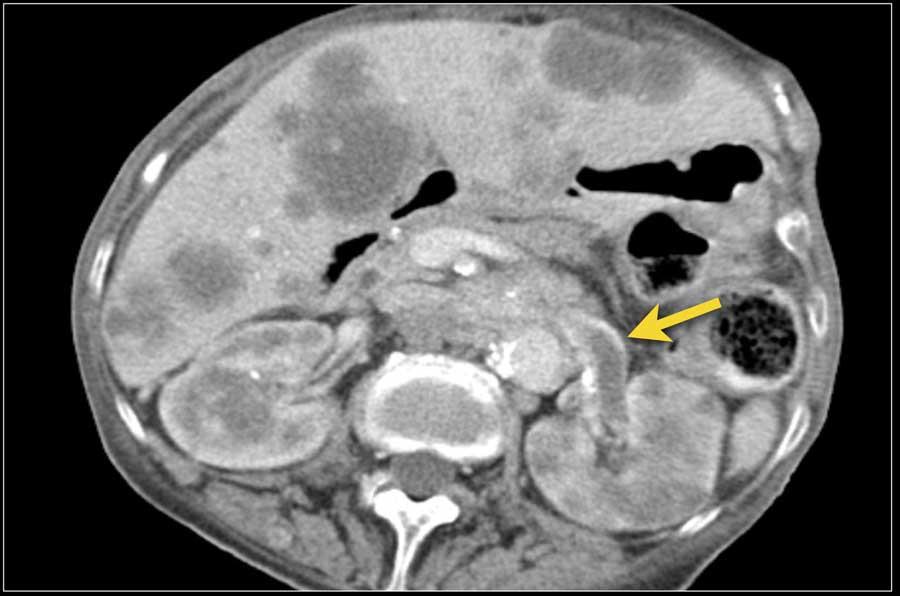

Áp xe thận có thể có thành dày, không đều, ngấm thuốc kèm xâm lấn mỡ quanh thận (hình).

Ở những bệnh nhân có biểu hiện lâm sàng không điển hình, hình ảnh nang phức tạp và lan rộng vào mỡ quanh thận có thể mô phỏng ung thư biểu mô tế bào thận.

Bệnh nhân này có biểu hiện điển hình với đau hông lưng phải và các kết quả xét nghiệm phù hợp với nhiễm trùng đường tiết niệu.

Hình ảnh siêu âm cho thấy một tổn thương giảm âm với một số vùng trống âm, gợi ý thành phần chứa dịch bên trong.

Tổn thương này được xác định là áp xe.